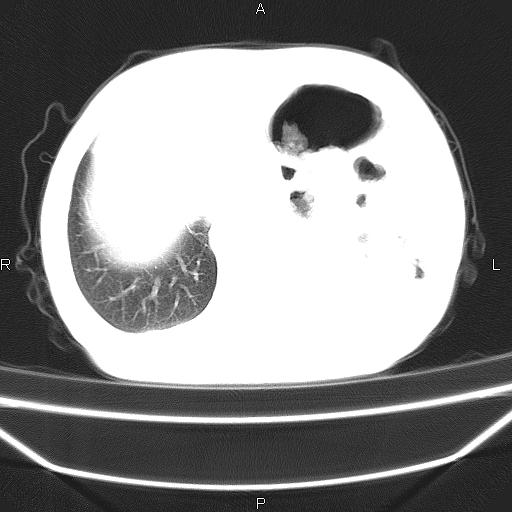

患者,男。50岁。近几日有咳嗽症状,无其他不适,既往病史无,考虑膈疝。请前辈们看看指导指导。

膈膨升,左下肺通气不良,膈肌好像还完整。

考虑左侧膈疝。

左侧膈疝。

符合隔膨升,膈肌较完整。